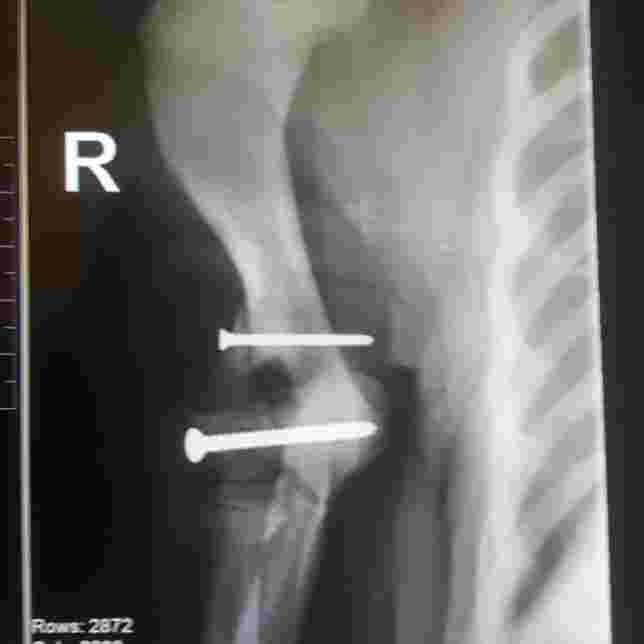

Our French bulldog broke his elbow when he was 3months old, he had surgery and got two screws put it. He is now going on 7months old and his leg seems to be giving him trouble this week, he woke up one morning and was limping and couldn't put much pressure on it but it improved itself within a few hours and he was perfect again. Now again tonight - 3 days later he is starting to limp on it again, it was perfect in between the 3days. What could be the issue? Thank you

Koby is a cutie! Ideally he just sprained his forelimb/only has a soft tissue injury and will respond well to a non-steroidal anti-inflammatory (recent blood work showing normal liver values is usually recommended before prescribing NSAIDs such as carprofen/Rimadyl) for a few days along with activity restriction for a week. This conservative therapy may be chosen as long as the limb does not appear swollen, acutely painful, etc. on physical exam/palpation. Re-x raying that limb would be ideal to determine if there has been migration of the pins/a new fracture etc. but could potentially wait if he is putting weight on the limb/it does not appear swollen/ and he responds well to the pain medication. As he has pins in his limb, he will be more prone to arthritis as the years go by and would likely benefit from being on a joint supplement such as VetriScience Mobility Flex or Vetriflex for life. Best of luck!